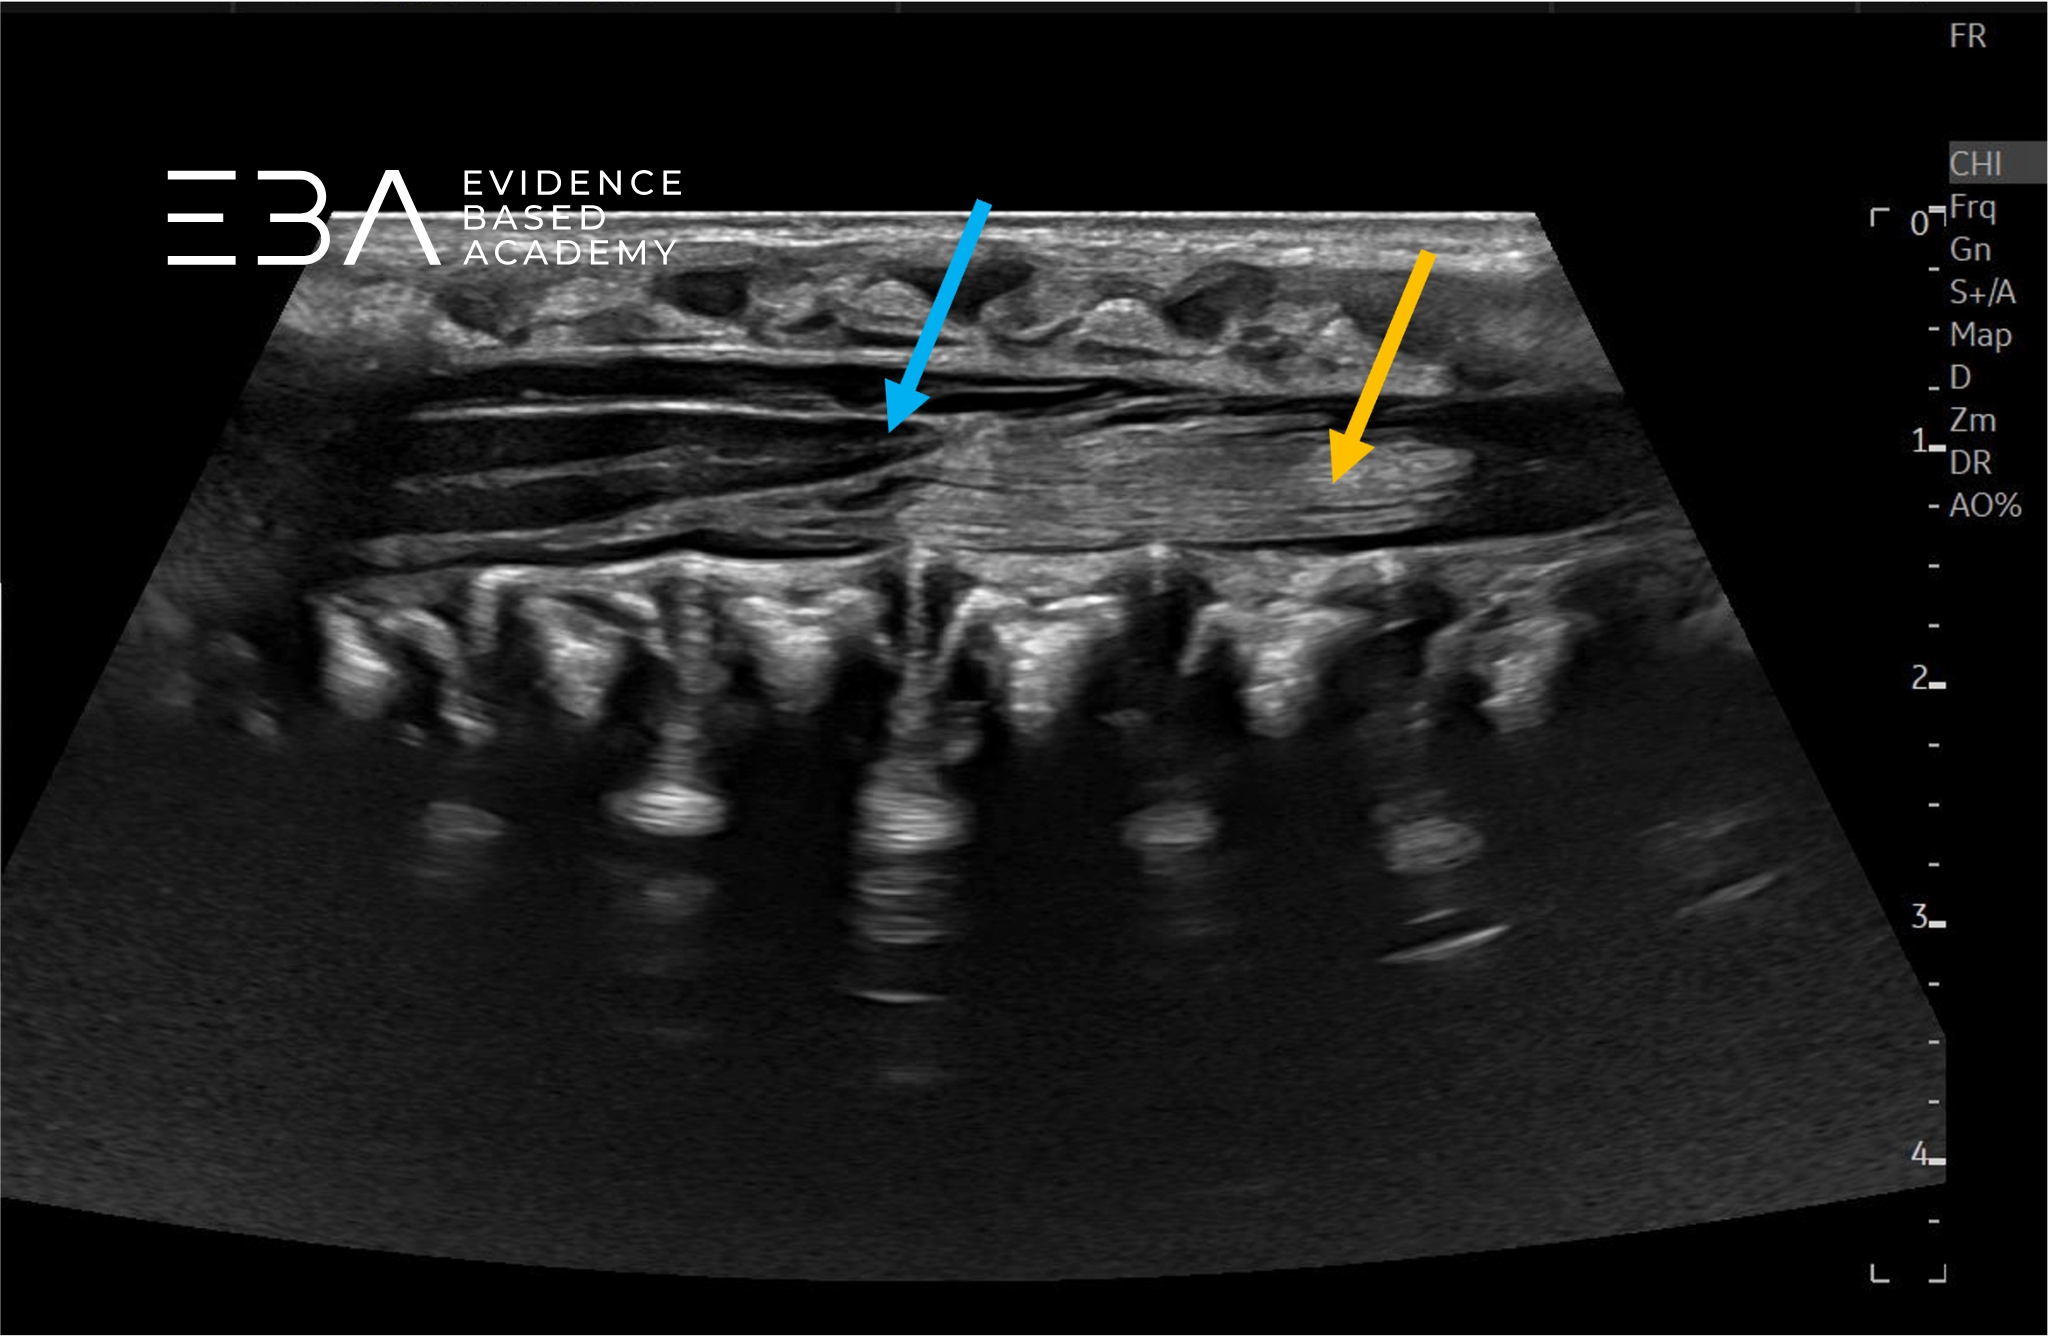

Obrazowanie dynamiczne

W trakcie USG kanału kręgowego należy przeprowadzić dynamiczną ocenę ruchomości rdzenia kręgowego i korzeni nerwowych. W niektórych przypadkach pomocne może być również USG w M-mode.

Należy pamiętać, że prawidłowy, nieuwięziony rdzeń również może nie wykazywać znaczącej pulsacji przez kilku pierwszych tygodni życia, co częściowo przypisuje się zmniejszonej objętości płynu mózgowo-rdzeniowego, wynikającej z fizjologicznego odwodnienia noworodków.

Przekrój podłużny przez kanału kręgowego – widoczna ruchomość ogona końskiego.